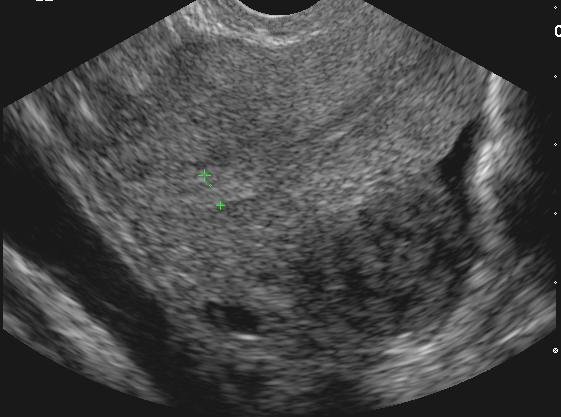

Myome sous-séreux (Cliché : Dr. C. TALMANT)